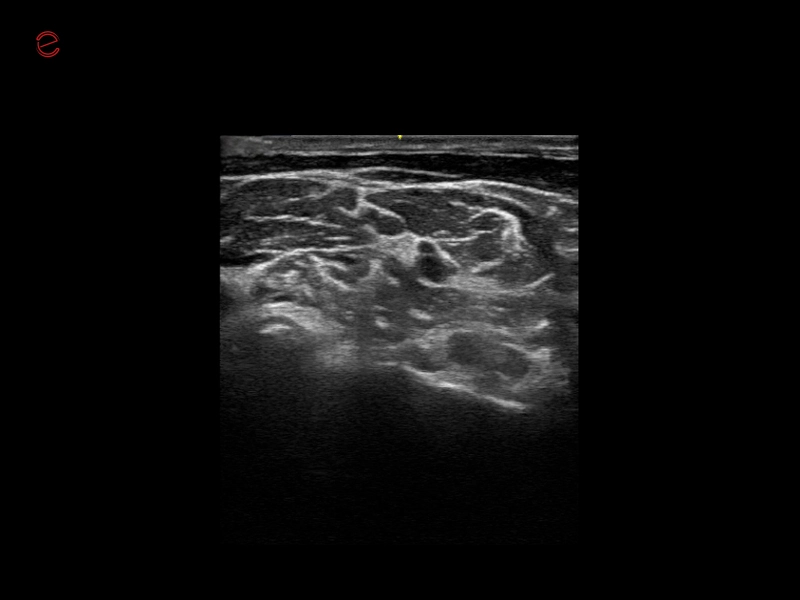

MyLab™9 Platform - Very-superficial linear imaging with Power Doppler algorithm

MyLab™9 Platform - Very-superficial linear imaging with Power Doppler algorithm